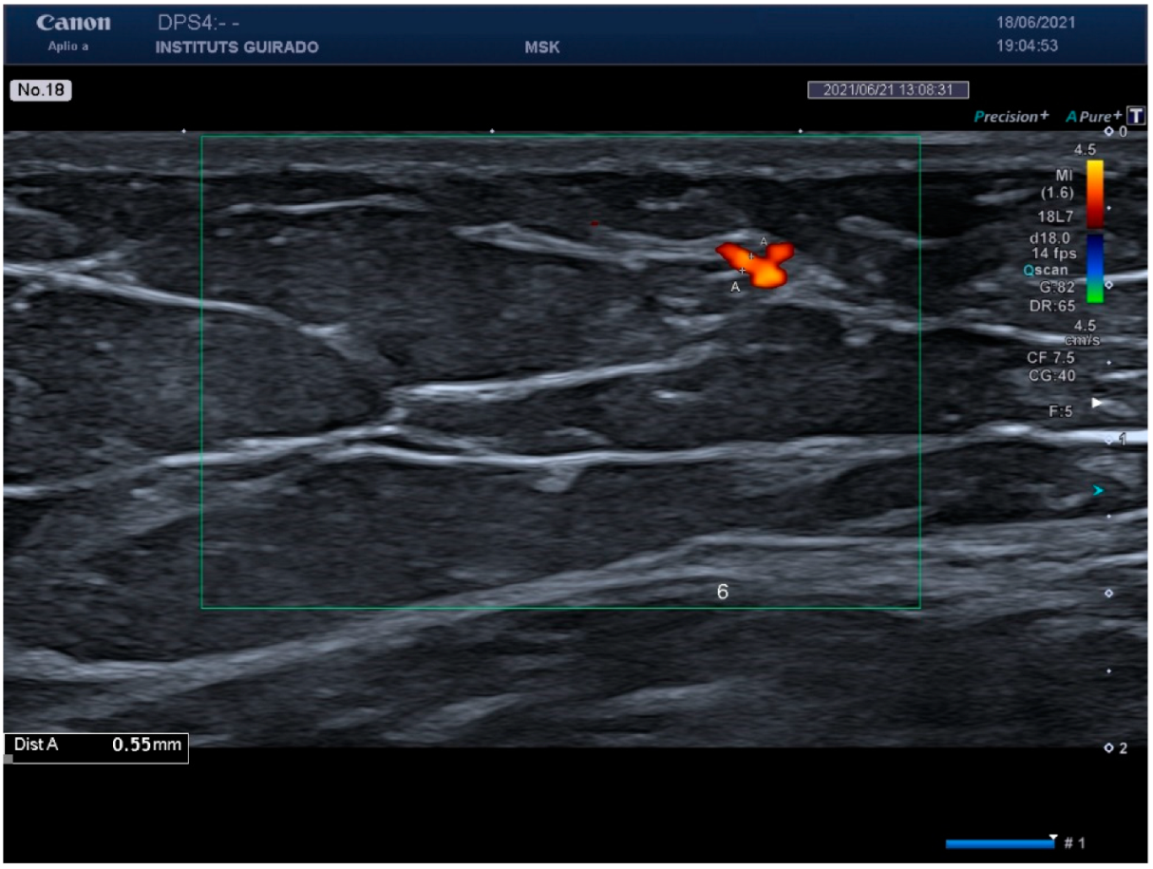

| Vessel diameter (mm) | 0.53 (0.45–0.59) | 0.46 (0.36–0.65) |

| Vessel diameter (mm) | 0.55 (0.47–0.94) | 0.47 (0.37–0.61) |